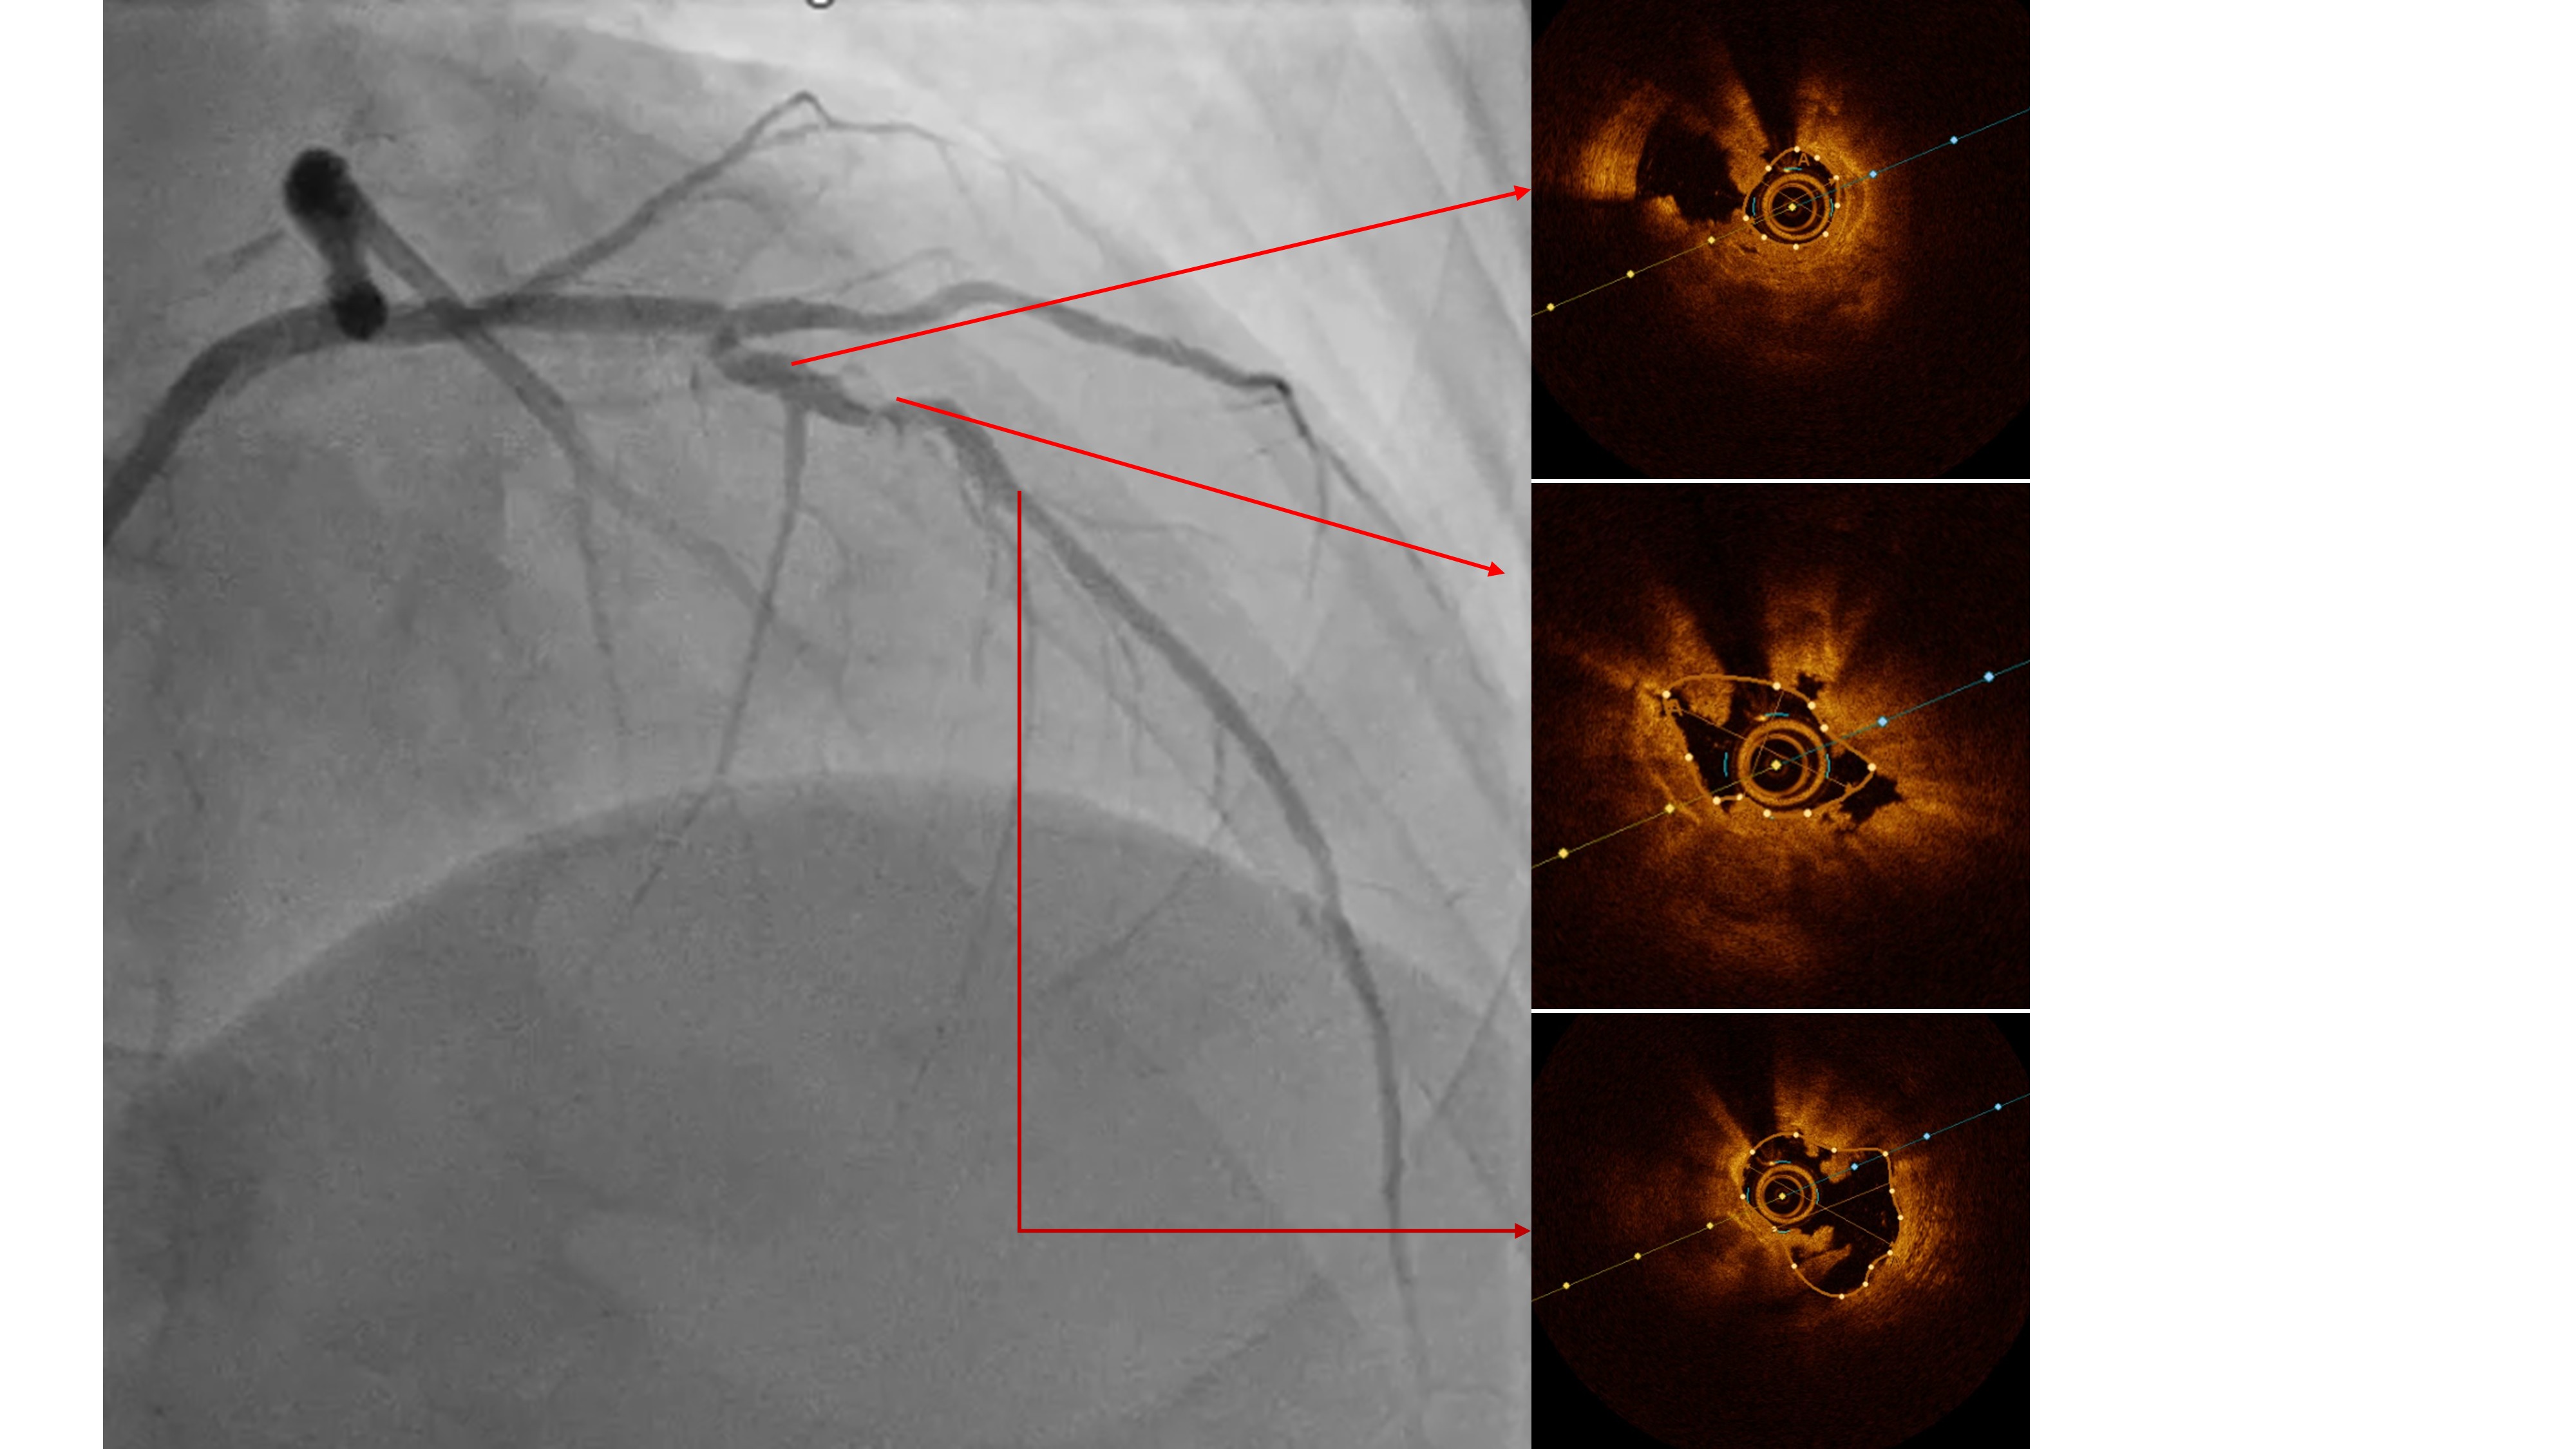

Two months ago, PCI of the LAD wasattempted. The guidewire successfully crossed to the distal LAD, but a 2.5 mmscoring balloon could not cross the mid lesion and showed a ¡°dog-bone¡±appearance upon inflation, so the procedure was stopped, and PCI of the LCx wasperformed instead. We reattempted PCI of the LAD using a Mach CLS 7 Fr guidingcatheter. A Fielder XT wire crossed to the distal LAD, but the OCT cathetercould not cross the lesion. Lesion preparation with a 2.0 mm scoring balloon athigh pressure and a 2.0 mm Wolverine cutting balloon enabled OCT passage. OCTimaging revealed fibrous and nodular calcification in the mid LAD, with aminimal lumen area of 1.71 mm and reference diameters of 4.0 mm (proximal) and3.3 mm (distal). Orbital atherectomy using a Diamondback 360 (1.25 mm crown)was performed carefully due to vessel tortuosity, with 10 runs at80,000–120,000 rpm. Post-atherectomy OCT showed reduced calcium burden andincreased lumen area. Further lesion preparation with 2.5 and 2.75 mm scoringballoons showed no ¡°dog-bone¡± sign, indicating adequate calcium fracture. A 3.0¡¿ 46 mm Amphilimus DES was implanted in the proximal–mid LAD and post-dilatedwith a 3.5 mm NC balloon. Final angiography showed TIMI 3 flow withoutdissection. Post-stent OCT showed good apposition, MSA 8.84 mm©÷ proximally and5.73 mm©÷ distally, with 99% expansion. The patient remained hemodynamicallystable and was discharged the following day.